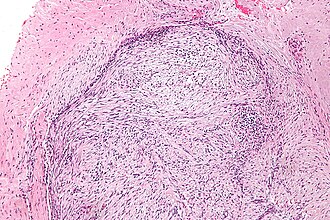

Nodular fasciitis. H&E stain.

LM usu. well-circumscribed, clusters of (non-pleomorphic) spindle cells, inflammation (lymphocytes), microcysts in cellular regions - uncommon, mitoses - common, extravasated RBCs.

• Usu. well-circumscribed.

• Clusters of (non-pleomorphic) spindle cells.

• Inflammation (lymphocytes).

• Microcysts in cellular regions - uncommon - discriminatory.

• Mitoses - common.

• Extravasated RBCs.